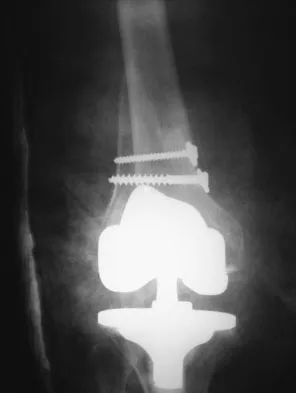

Practice Orthopedics online MCQs and assess your clinical knowledge. High-yield questions for medical students and orthopedic residents.